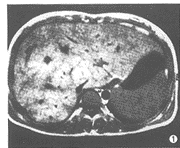

19例中,肝脏增大18例(95%),尾叶增大14例(74%)。14例(74%)肝脏信号不均,T2WI呈斑片状稍高信号,T1WI呈稍低信号且较明显(图1~3)。7例(37%)显示下腔静脉入右心房处阻塞;4例(21%)下腔静脉内有血栓影,表现为T1WI呈等信号,T2WI呈稍高信号;下腔静脉肝后段裂隙样狭窄10例(53%)。19例(100%)均显示肝静脉狭窄或阻塞,其中累及左肝静脉15例,中肝静脉13例,右肝静脉11例。17例(89%)见有肝内侧支血管呈“逗号”样或迂曲、走行无规律的血管影,5例(26%)显示有副肝静脉,呈粗大的血管影自肝右叶连于下腔静脉的右侧壁(图4~6)。17例(89%)见有肝外侧支血管,其中7例腹壁静脉曲张,14例(74%)有粗大的奇静脉和/或半奇静脉影,膈下静脉曲张3例,胃底静脉曲张3例。脾脏增大16例(84%),7例(37%)有腹水。

图1 T1WI显示肝脏增大,信号不均匀,肝内见不规则形且

走行无规律的侧支血管影,下腔静脉受压变窄

超声、CT、静脉造影是BCS的常用检查方法,其中静脉造影是诊断以及介入治疗本病的主要依据。静脉造影可以明确狭窄或阻塞的部位和类型,了解侧支血管。MRI检查有无创性、多平面、多参数等优点[1~4],对于显示肝脏大小、形态以及邻近的实质性脏器优于超声和静脉造影。BCS常表现为肝脏增大,本组有18例显示肝脏增大。尾叶由于有单独的静脉回流到下腔静脉,增大较明显,本组有14例。区域性肝脏充血、中央小叶坏死及含水量的增加使得肝脏信号不均匀[3],T1WI呈低信号,T2WI呈高信号。T1WI、T2WI均呈低信号则提示肝纤维化。本组中14例有肝信号不均的表现,T1WI显示例数较T2WI稍多。